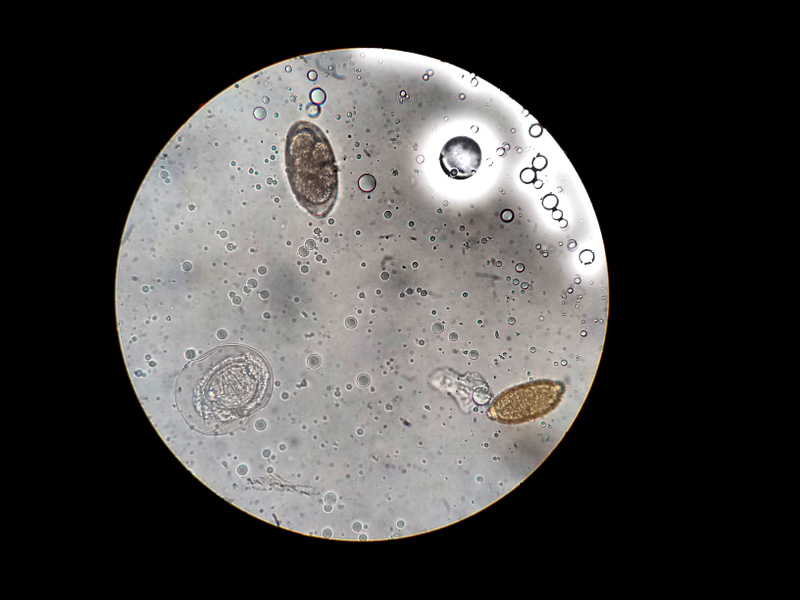

- Ácaros (principalmente sus heces).